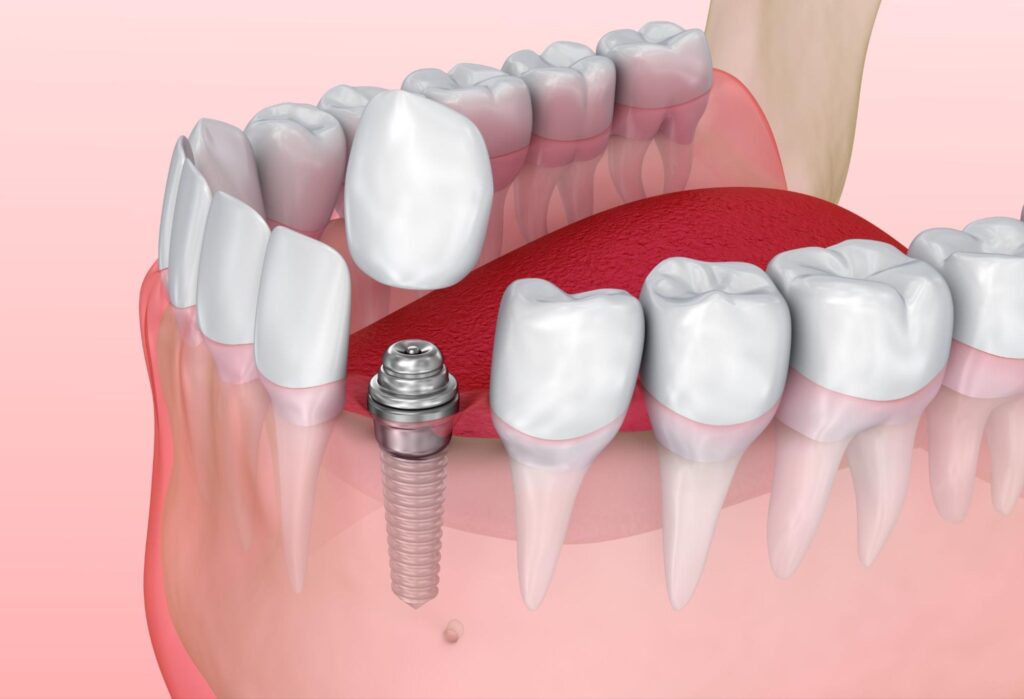

インプラントの構造

インプラントは、インプラント体(人工歯根)、アバットメント(支台)、上部構造(人工歯)という3つのパーツで構成されます。

| インプラント体(人工歯根) | 顎骨の中に埋め込み、骨と結合して土台を形成 |

| アバットメント(支台) | 人工歯根と人工歯をつなぐ連結部 |

| 上部構造(人工歯) | セラミックやジルコニア製で審美性に優れ、自分の歯に近い見た目を実現 |